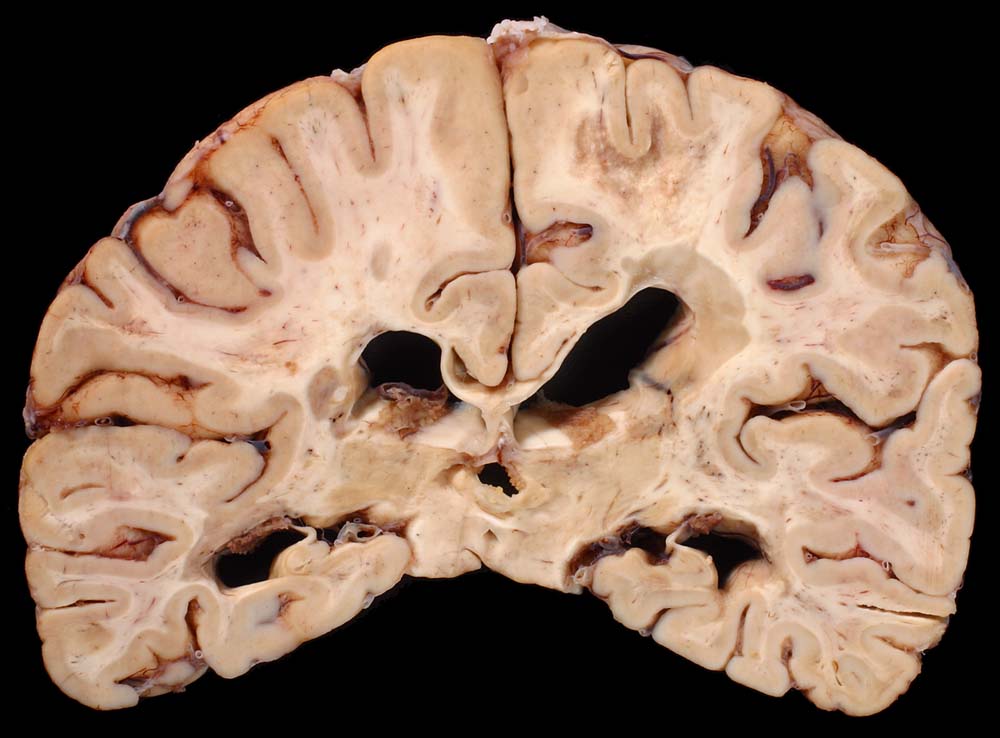

Periventrikulär betonte fleckförmige Grauverfärbung des Marklagers ( Entmarkungsareale).

Chronische und aktive Entmarkungsareale in der weissen Substanz (beidseits, periventrikulär betont).

Diagnose einer multiplen Sklerose vor 12 Jahren. Paraparese der Beine. Neurogene Blasenentleerungsstörung. Seit einem Jahr deutliche neurologische Verschlechterung.